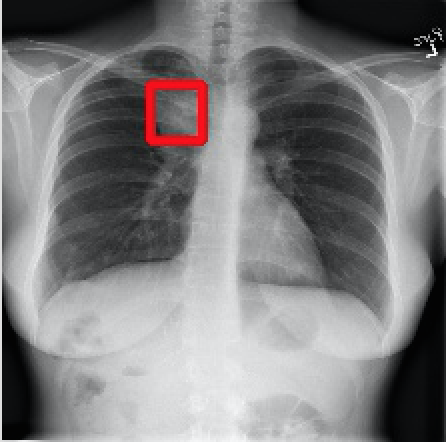

2017年CVPR的一篇“ChestX-ray8”论文[1]首次对医院留存的胸部CT数据库进行人工处理,并通过医学专家分别对8种疾病作标记,形成该领域首个标准的数据库,为胸部医疗的计算机辅助诊断打开了大门,也为后续的研究提供铺垫。CT数据库整理的效果如下图所示,其中红线框内为人工标注的疾病区域:

Atelectasis Cardiomegaly Effusion Infiltrate

Mass Nodule Pneumonia Pneumothorax

图2.1 胸部数据集示例

目前为止,数据集已经达到了14个疾病的分类结果,每张图的大小为1024×1024,少数图片附有由专家标注的病理区域,数据集共有112120张图片,来源于30805个不同的病人,其中51708张图片被标注有疾病,其余则为无病。可以看出无病的数据较多,对有病的特征学习可能较低,相关的学习加速收敛的方法将在2.4节讲解。